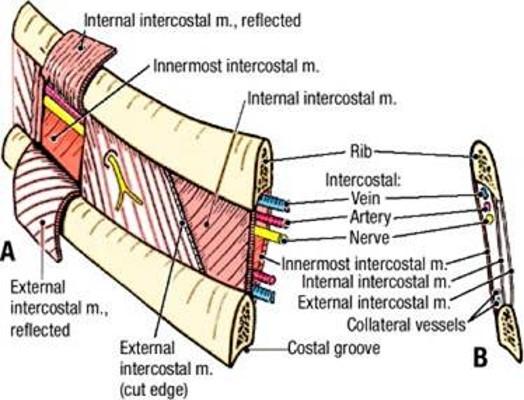

identify the actions of these muscles and their relationship to each other in space?

- External intercostals (E)

- Internal intercostals (I)

- Innermost intercostals (IM)

External intercostals (E)...inspiration...most superficial

Internal intercostals (I)...expiration

Innermost intercostals (IM)...elevate?…not completely understood...most deep

what is between the internal intercostals and the innermost intercostals? which muscle is on top?

when looking at a picture how do you identify these muscles, what should you look for?

BV's and nerves in between them

internal intercostal on top

basically, look for the innermost muscle and if its muscle colored it is the innermost intercostals...if it looks like a layer was peeled and you see nerves traveling horizontal, it indicates that you are looking at the internal intercostals

notice the external intercostal muscles

look at picture

what muscle do you see here and how do you know?

innermost intercostals because you can see the nerve and vessels driving into the muscle indicating that you can see the innermost intercostals (you are looking inside the chest so the IM are the deepest muscles inside)

what supplies the intercostal spaces? what is the spacial relationship of these things that enter the intercostal space?

12

Anterior rami supplies the intercostal spaces

“VAN” – vein, artery, nerve bundle entering the intercostal space (from top to bottom)

what are these nerves that are going horizontal?

follow how it curves around and notice how it splits and then goes to the front and back

intercostal nerves

Identify/describe the intercostal artery pathway?

- Intercostal arteries/veins run in the ___________ aspect of

the intercostal space?

- They are ________ to the “superior rib” of the intercostal space?

- Collateral branches of intercostal arteries/veins run in the _________ aspect of the intercostal space

superior aspect

inferior

inferior

describe whats in the intercostal spaces from superior to inferior?

These travel in intercostal space together just ________ to rib

- There is a second set of smaller collaterals located ________ to each rib

- Vein

- Artery

- Nerve

inferior

superior

notice in picture how the vein artery and nerve (VAN) is just below the rib and then more down in the intercostal space just above the rib are the collateral vessels

vein, artery and nerves are located just ______ each rib?

what is a thoracentesis? what do you want to avoid when you insert the needle? overall, where do you wanna put the needle?

below

- Procedure to remove fluid from pleural cavity

- Avoid damage to intercostal structures (and lung) when inserting needle

put the needle on the superior margin of the rib...avoids hitting the VAN's